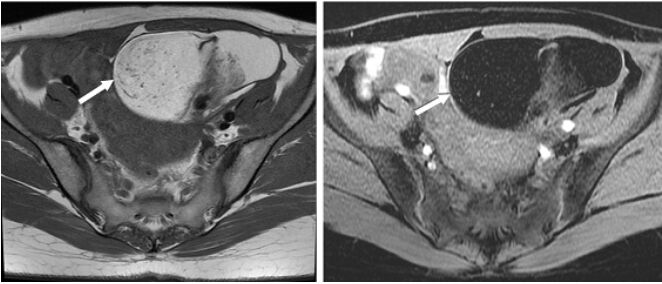

74.一位年輕女性接受磁振造影檢查發現卵巢腫瘤如圖,箭號所指之病灶,下列何者為最恰當之診斷? (A)畸胎瘤 (B)血腫 (C)黃體囊腫 (D)巧克力囊腫